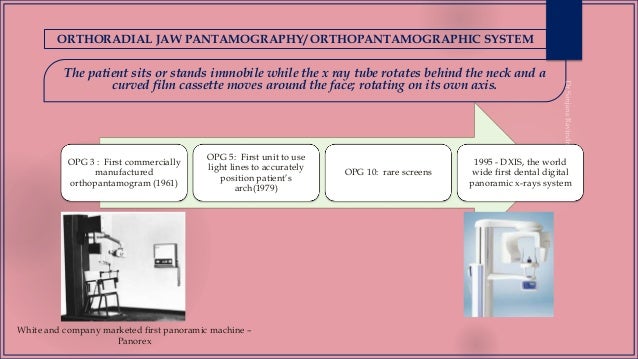

This position is often referred to as the patient being positioned with the ala tragus line in a minus 50 position. At the same time this position allows the ala tragus line to be correctly positioned. The panelipse panorex i and panorex ii use the ala tragus line for patient positioning. Notice the panoramic image is divided into 9 areas that make up the 6 zones that you must learn to picture each panoramic radiograph or image in your mind s eye.

Tragus of the ear must be aligned with the plastic guides ala tragus line should be 50 from level positioning the patient position the patient panoramic lead apron must be used position apron high in front to protect the thyroid apron should be lower in back to expose the neck. Discussion most panoramic x ray machines use the ala tragus line for patient positioning whereas a few use the orbito meatal line. Ala tragus line is one of the common extra oral soft tissue land mark utilized in dental clinics for occlusal plane orientation. Here the occlusal plane should be mildly curved upward to make a smile like line.

White philadelphia pennsylvania in addition to the ala tragus line uses an occlusal plane line on the cassette carrier for patient positioning. Pate b d s m s and l. The part of a panoramic x ray machine where the cassette is positioned for exposure. The horizontal plane in patient positioning for panoramic radiography j.